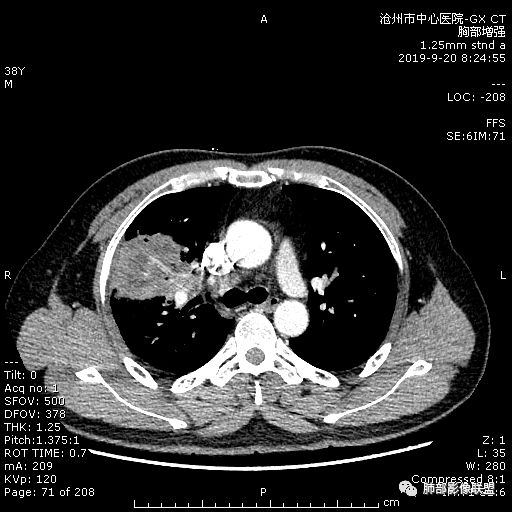

青年男性,肿瘤指标无异,右上中肺团片影,形态不规,跨叶生长,

病灶内见坏死,增强边缘强化,考虑炎性肉芽肿,TB,鉴别鳞。

年轻男性,咳嗽2月,痰中带血,胸痛,炎症指标稍高,肿标正常。影像,右肺上叶不规则团块影,浅分叶,伴边界不清磨玻璃影,从外周向内分布,局部胸膜增厚,病灶中央坏死,坏死边界尚清,空洞形成,空洞内壁光滑;考虑炎性肉芽肿性病变,结核可能,鉴别恶性肿瘤及真菌感染。病灶分布特点不考虑隐球。

右肺上叶不规则病灶,密度不均,有分叶,边缘不清,中央有坏死,坏死壁尚光滑,增强壁有强化,病灶有外朝内,整体收缩为主,慢性病程,考虑炎性病变,肺脓肿或者结核,淋巴结肿大,支气管截断,胸膜脂肪间隙变窄,加个鉴别恶性肿瘤。

近端支气管截断,非坏死区的强化特征,肺门区肿大淋巴结,所谓的“月牙铲”,这些强烈提示病变是癌;胸膜、相邻肋间肌的改变,提示是炎性改变;在癌与炎性肉芽肿之间,哪个占主导地位?是解决问题的关键;坏死区的形态,也支持炎性病变。

右肺上叶分叶状肿块(冠状位尤为明显),内见液化坏死,支气管截断,收缩力强,周围有片状影,右侧腋窝及纵隔淋巴结增大,增强有强化,定性恶性病变,脓肿形态及临床症状不符,暂排除。

右上肺占位,总体膨胀性生长,支气管截断,坏死明显,常规考虑鳞。

38岁,男性,慢性咳嗽2月,右胸痛8天,无发热;白细胞高,肿瘤标志物不高;右上肺不规则块状影,周围有磨玻璃影,边界清,整体有膨胀感,分叶,与胸膜糊墙,并见栽赃,增强肿块中央坏死,周边强化。综合考虑,考虑恶性,鳞癌可能。

38岁,男性,慢性咳嗽2月,右胸痛8天,无发热。白细胞高,肿瘤标志物不高。右上肺不规则块状影,周围有磨玻璃影,边界模糊,整体有膨胀感,分叶,与胸膜糊墙,可疑栽赃,增强肿块中央坏死,边界清,周边强化明显,强化区有低密度影,壁不规则,跨叶生长,支气管截断,伴支气管扩张,综合考虑腺癌

中年男性,咳嗽2月,伴胸痛8天,少许痰血,无发热中性粒明显增高,低氧,肿标不高,右肺上叶不规则实性肿块,深分叶,局部凹陷呈月牙铲改变,多坏死,多空泡,前段支气管分支似见堵塞,2R、4R、10R和7区淋巴结肿大。考虑肺癌可能,建议支气管镜活检

晨读病例,右肺上叶胸壁处占位,边缘分叶毛刺,收缩力强,多发坏死,远端支气管截断,不均匀性强化,血管穿行变窄,纵隔多发淋巴结肿大,考虑恶性肿瘤,首先考虑腺癌

膨隆、深分叶,支气管截断,叶裂推移,淋巴结肿大,均提示恶性可能;但毕竟年轻,血象高,内部坏死边界清晰,局部收缩感,提示感染可能,另外内部数个小空洞改变,是扩张支气管吗?需要连续层面看,如果是,就更支持感染。

右肺上叶不规则实性肿块,有膨胀有收缩,多坏死,空泡,右肺门淋巴结肿大,考虑肺癌,就是才38岁,太年轻了

晨读:青年男性,咳嗽痰中带血,亚急性起病,白细胞高,超敏高,CT示右肺上叶分叶肿块,内部坏死,病灶周围小结节,近端支气管通过,纵隔淋巴结肿大,综合考虑肉芽肿型结核较鳞癌可能大

晨读:右肺上叶不规则团块,深分叶,膨胀为主,有部分收缩,叶间裂牵拉上移,内多液化坏死,有支气管扩张,右肺上叶大支气管近端通畅,远端堵塞,说明肿块来源于外周,纵隔及右肺门淋巴结肿大,胸膜糊墙为主,年轻人,肿标不高,炎性指标高,综合考虑炎性肉芽肿放前面脓肿,结核,肿瘤放后面。

良孑: 晨读病例,右上肺不规则实变,边界模糊,内可见多发坏死灶,腔内坏死壁厚薄不均,有支气管截断,强化时病灶内血管受累,右肺门淋巴结肿大,从影像上看恶性鳞癌征象较多,但病变明显强化,且坏死壁是均匀强化,炎性标志物高,患者年龄较轻,病史较长,病灶内多个坏死液化灶且内缘光整,综和判断,首先考虑亚急性肺脓肿,其次考虑鳞癌

病灶垮叶,强化明显,病灶内见坏死、空泡,周围模糊,考虑放线菌病?鉴别鳞癌

青年男性,右肺上叶肿块,分叶,明显膨隆,内见空洞与支气管相通,增强环形强化,中心液化坏死。实验室鳞癌指标不高。考虑:1,结核,2,肺脓肿。鉴别鳞癌。

中年男性,咳嗽2月病史伴胸疼。白细胞及中性粒细胞高。右上肺团块影,边缘平直内收,与胸膜宽基底相连,胸膜肥厚,肿块内多灶性坏死,有空泡征,支气管进入,走行自然,近端有阻塞,考虑感染性疾病,肺脓肿。但是有深分叶,鳞癌合并感染也不排除。

右肺上叶不规则病灶,密度不均,有分叶,边缘不清,中央有坏死,坏死壁尚光滑,增强壁有强化,考虑肺脓肿或者结核,但是淋巴结肿大,支气管截断,不除外肿瘤。